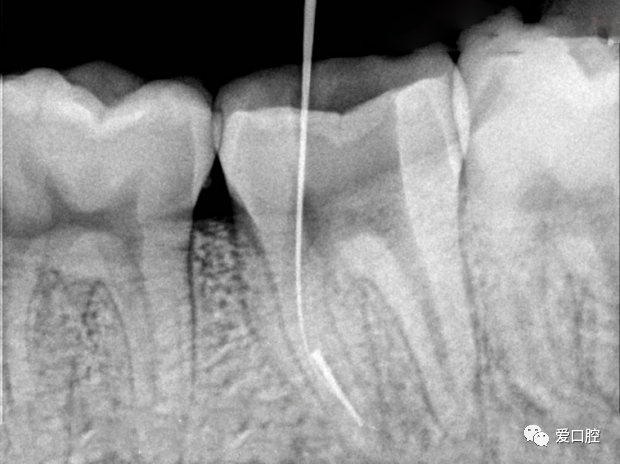

尊敬的医生,我做根管治疗时断针,现在牙齿没有症状,请问下一步该如何

取断针